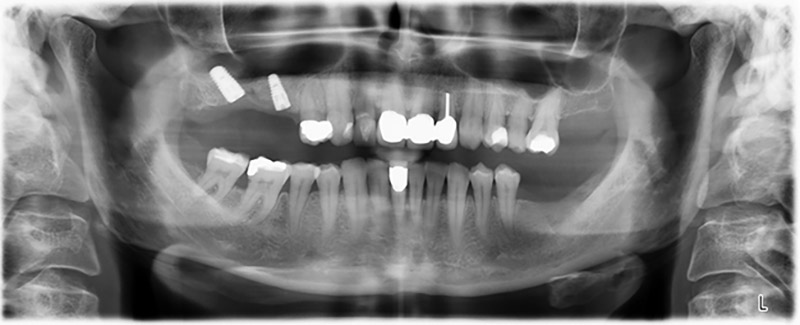

About six months after teeth 16 and 14 were extracted, a digital volume tomography (DVT, Planmeca) examination was performed for planning and risk minimization purposes. It clearly showed that the bone had not regenerated to the desired volume (Fig. 2 to 7).

A sinus floor elevation was required in both regions 16 and 14 to guarantee a fixed restoration based on at least two implants. Relatively large-scale bone augmentation was required due to the residual bone volume being extremely low in this case. Major bone augmentation procedures are invasive and linked to higher patient morbidity, as well as being time-consuming and expensive. It is more difficult to predict the results of the treatment and the risk of failure is increased. The patient was informed of the increased risk and was offered a removable solution, which she consistently rejected.

To restrict the augmentation to region 14, and in consultation with the patient, it was planned that implant 16 would be placed, inclined, in the dorso-cranial direction (Fig. 8).